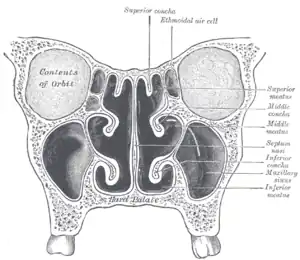

Sur les côtés latéraux on a trois cornets qui offrent une résistance à l'écoulement de l'air et le dirigent vers l'épithélium olfactif en haut.

Les cornets sont une superposition d'os longs, étroits et courbes (en forme de coquillage étiré), recouverts d'une épaisse couche de tissu, très vascularisée, érectile et glandulaire.

Ils sont placés latéralement dans les cavités nasales et s'enroulent de façon médiale et vers le bas à l'intérieur des voies respiratoires nasales.

Il y a trois cornets dans chaque cavité nasale :

- le cornet inférieur : le plus grand, aussi long que l'index;

- le cornet moyen : aussi long qu'un auriculaire ;

- le cornet supérieur : très petit.

Les deux cavités nasales sont séparées par la cloison nasale appelée septum.

Les cornets divisent les voies respiratoires nasales en 3 passages aériens semblables à des sillons, les méats inférieur, moyen et supérieur, forçant ainsi l'air turbulent à s'écouler selon un flux laminaire autour de la plus grande surface possible de cils et de tissu. Les cornets sont essentiellement le radiateur et le moteur du nez.

La majeure partie du flux d'air inhalé voyage dans le méat moyen, entre les cornets inférieurs et les cornets moyens.

Les cornets moyens sont plus petits et se projettent vers le bas à partir des sinus ethmoïdes. Ils abritent les ouvertures jusqu'aux maxillaires et aux sinus ethmoïdes et agissent comme des tampons d'air pour que les sinus ne soient pas en contact direct avec le flux d'air pressurisé nasal.

Les cornets supérieurs protègent le bulbe olfactif et sont également innervés avec une multitude de terminaisons nerveuses olfactives qui se prolongent quelque part dans les cornets moyens.